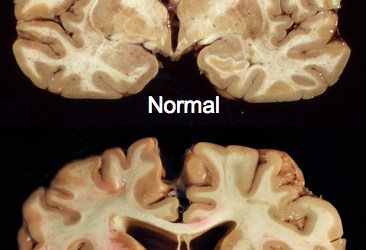

This may be of interest to some of you guys. Earlier today, I posted something about the late hockey player, Derek Boogaard, and his probable struggles with CTE. There has been some follow-up research done that shows CTE impacts athletes differently than the rest of the population. Any profession that runs the risk of head injury can leave people with this debilitating disorder, but athletes – especially football and hockey players – can be especially susceptible. From The Canadian Press: